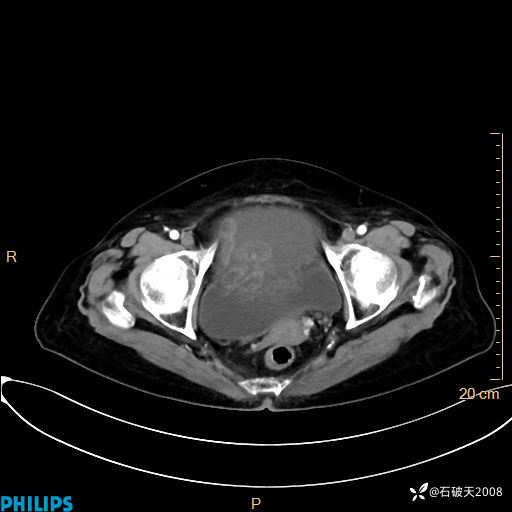

平扫